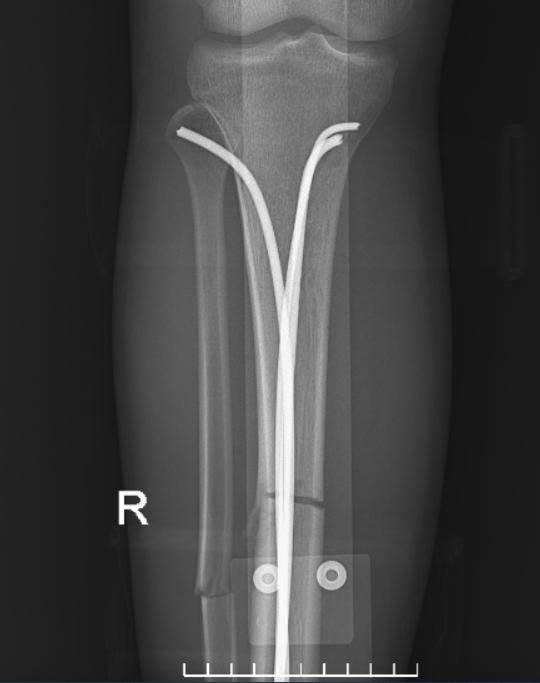

Sau hội chẩn chuyên môn, người bệnh được chỉ định phẫu thuật kết hợp xương dưới hướng dẫn của hệ thống màn hình tăng sáng (C-arm). Đây là thiết bị hiện đại hỗ trợ bác sĩ quan sát rõ vị trí ổ gãy trong suốt quá trình phẫu thuật, giúp nắn chỉnh xương về đúng trục giải phẫu và đặt dụng cụ cố định xương một cách chính xác, hạn chế tối đa sang chấn cho người bệnh.

Ca phẫu thuật được tiến hành ngay trong đêm và diễn ra thuận lợi. Các bác sĩ đã cố định vững chắc ổ gãy, xử trí tốt phần mềm và vết thương hở, tạo điều kiện thuận lợi cho quá trình liền xương và phục hồi chức năng vận động. Sau 6 ngày điều trị, tình trạng người bệnh ổn định và được xuất viện theo đúng dự kiến.